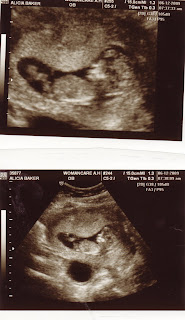

Here's a couple of profile pics from the scan. I told Bob I think it looks like my nose from the profile shot :)

The OB appointment went great. I had the ultrasound first and I love the tech at the office. She took her time explaining everything and pointing things out. I think that baby was sleeping because he/she didn't move much at all (except to rub their eyes at one point). They were in the exact position they needed to be in to get the measurement of the neck. Our measurement was 19, which is a great number anything over 30-35 is cause for concern the tech said. I still have to wait to get the 1st set of blood work results back but the tech said she wouldn't worry about a thing and it seems that we have a perfectly healthy baby in there. She didn't try to even get a gender shot so I'll just have to be patient! I did post the profile shot of the baby on a website I go on and there is a way that you can get a really good guess at the gender by looking at a nub in that area and people seem to think by the nub it looks like we are having a girl but who knows! So we'll find out for sure in 8 weeks! That is when my next ultrasound is, I am going to have major withdrawls by then! I have an appointment on July 11th for the 2nd set of blood work and just a check up with the doctor. I think the best part of this appointment was hearing the beautiful sound of the heart beat! Oh my goodness, that was so unbelievable! Unfortunately I didn't get a chance to call Bob so he hasn't heard it yet but he will definately get to hear it on the 11th.